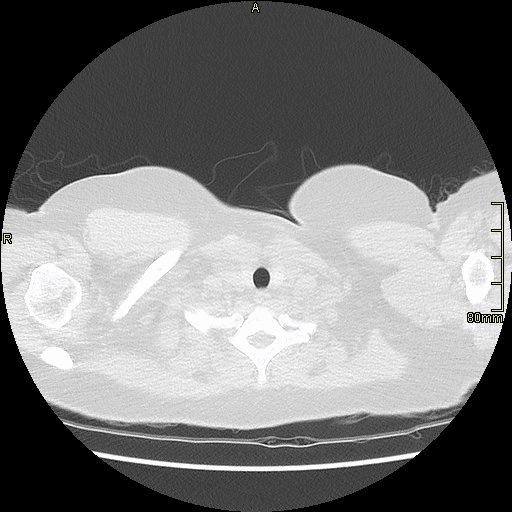

Example below is a General Chest/Abdo/Pelvis without contrast. Bony reconstructions are available depending on clinical question and differential diagnosis

Chest/Abdo/Pelvis (Axial)